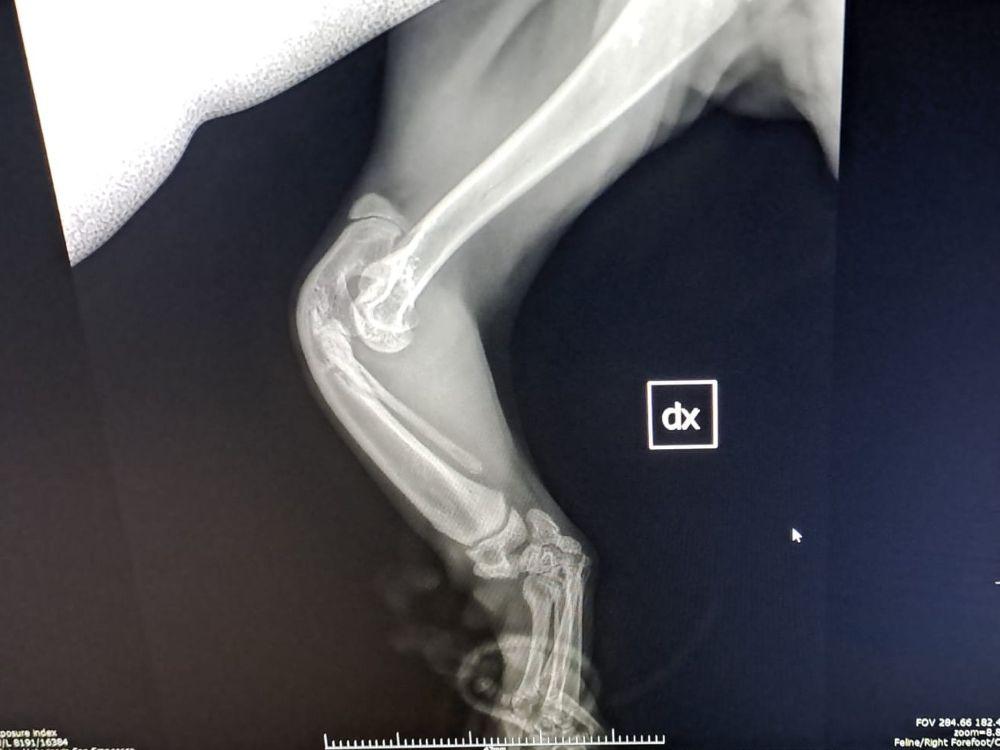

Pino, inzwischen acht Monate, hat seinen ersten Klinik-Besuch hinter sich. Seine linke Pfote wurde geröntgt um zu sehen, wie weit sich die Wachstumsfugen geschlossen haben. Insgesamt wurde er beim Besuch noch mal gründlich untersucht und sein Gangbild angeschaut. Beim Sprung kann er insbesondere links keinerlei Gewicht abfangen und stürzt dabei auf die Schulter.

Das Ergebnis: die nächsten Schritte können eingeleitet werden, denn Pino ist nahezu ausgewachsen. Nun wird im April ein dreidimensionales CT folgen, um die genaue anatomische Struktur seiner Vorderbeinchen darzustellen. Es wird sehr entscheidend sein, zu sehen, ob die fehlende Knochenstruktur durch ausreichend vorhandene Bänder und Sehnen ausgeglichen wird, um eine natürliche Stabilität der Beinchen zu gewährleisten. Dies kann man auf Röntgenbildern nicht erkennen. Der behandelnde Chirurg möchte, wenn sich alles nach Plan darstellt, nur Pinos linkes Handgelenk in die richtige Position bringen und versteifen. Doch soweit ist es noch nicht.